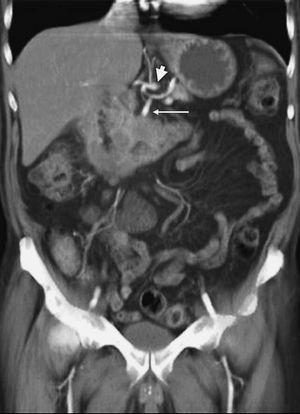

Metástasis hepáticas te;stasis hepáticas o peritoneales constituye un criterio definitivo de irresecabilidad tumoral, no obstante algunos estudios12,14,45 han sugerido la incapacidad de la TC para detectar lesiones metastásicas de pequeño tamaño (fig. 10). Vargas et al43, utilizando TCMC, presentan resultados similares, ya que de los 23 pacientes considerados resecables en base a los hallazgos de la TC, en 3 no se pudo llevar a cabo la resección. Dos de ellos presentaban metástasis hepáticas de pequeño tamaño y el paciente restante tenía pequeños implantes tumorales peritoneales. En nuestra experiencia32 la TC helicoidal bifásica tiene una baja sensibilidad para la detección de metástasis a distancia (55%), aunque con un alto valor predictivo negativo (90%) y una elevada precisión diagnóstica (88%).

Fig. 10.-. Estudio de tomografía computariazada en fase portal. Neoplasia de páncreas diseminada que dilata la vía biliar intrahepática. (A) Metástasis hepática subcapsular, infracentimétrica, hipodensa (flecha) en la fase venosa portal del estudio dinámico. (B) Se identifica una segunda metástasis (flecha) de menor tamaño, también subcapsular en el extremo hepático caudal.